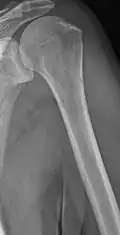

The diagnostic examination of a person with suspected multiple myeloma typically includes a skeletal survey. This is a series of X-rays of the skull, axial skeleton, and proximal long bones. Myeloma activity sometimes appears as "lytic lesions" (with local disappearance of normal bone due to resorption) or as "punched-out lesions" on the skull X-ray ("raindrop skull"). Lesions may also be sclerotic, which is seen as radiodense.[76] Overall, the radiodensity of myeloma is between −30 and 120 Hounsfield units (HU).[77] Magnetic resonance imaging is more sensitive than simple X-rays in the detection of lytic lesions. An MRI may supersede a skeletal survey, especially when vertebral disease is suspected. Occasionally, a CT scan is performed to measure the size of soft-tissue plasmacytomas. Nuclear Medicine Bone scans are typically not of any additional value in the workup of people with myeloma (no new bone formation; lytic lesions not well visualized on nuclear bone scan).

Multiple myeloma in the upper arm -

Femur with multiple myeloma lesions -

Same femur before myeloma lesions for comparison -

Humerus with multiple myeloma lesions -

Same humerus before, with just subtle lesions